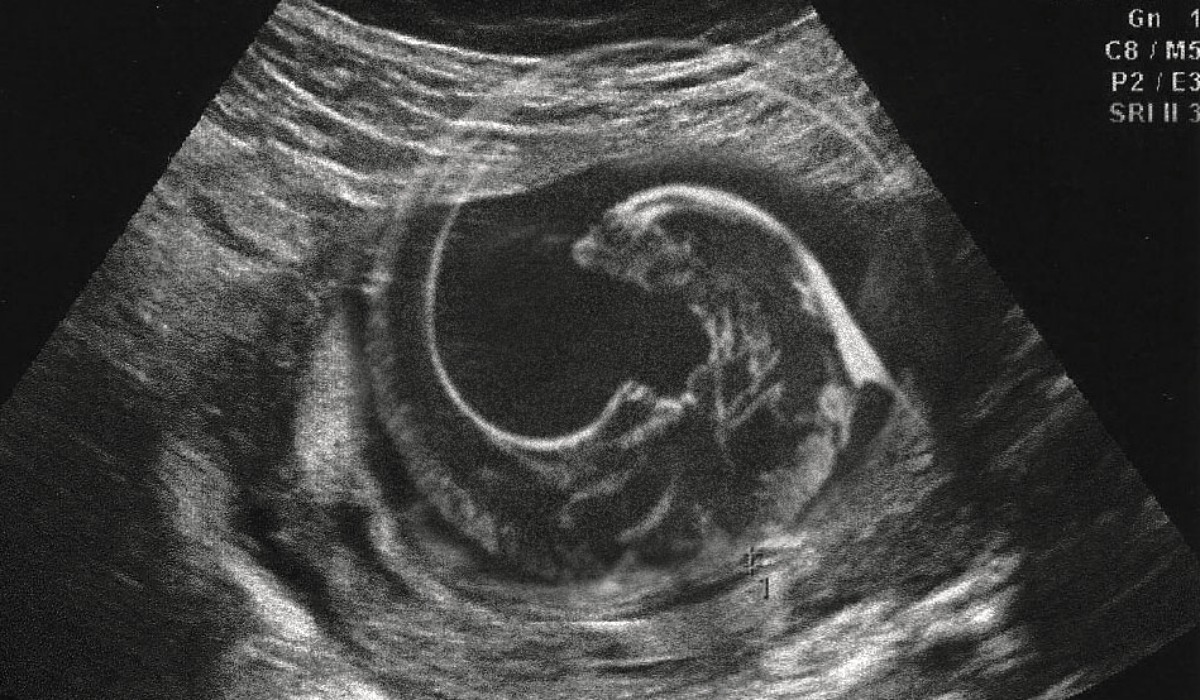

For the past 15 years, a teenager named Shahril from Sungai Petani has been living with the foetus of his twin inside him.

According to a report by Sinar Harian, when he was younger, Shahril noticed that his abdomen was getting more and more bloated by the day. It was during a medical examination that the doctors found the foetus.

When the foetus was removed, doctors confirmed that his ‘twin’ was a parasite and had hair, hands, arms and even genitalia.

According to the report, Shahril is the first reported case of “fetus in fetu” in Malaysia.